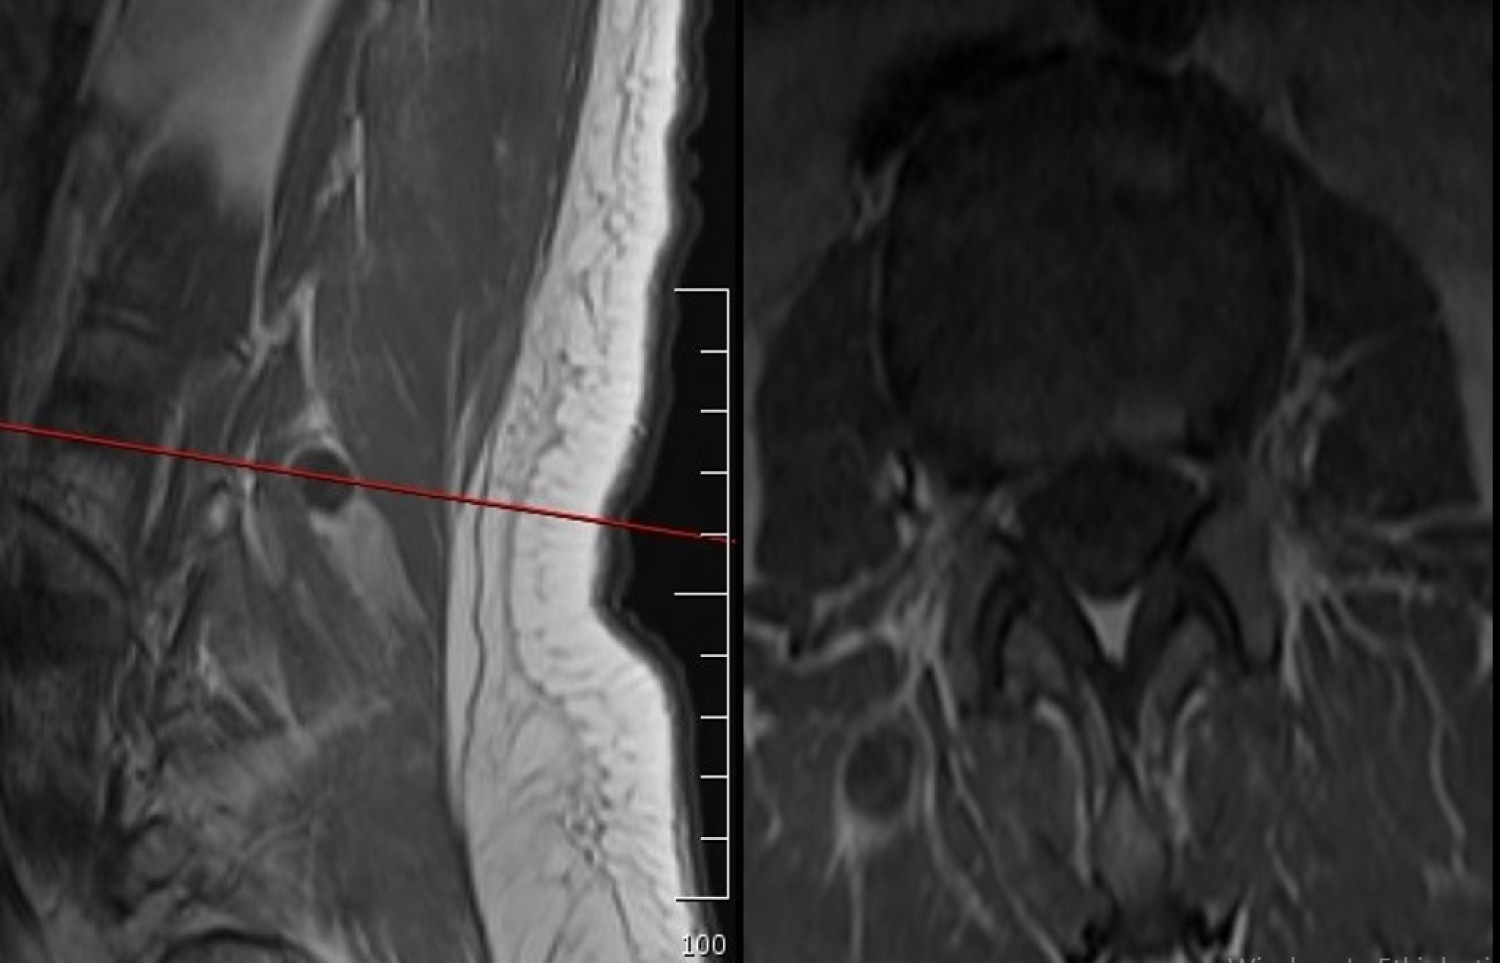

Magnetic resonance myelogram showed no cerebrospinal fluid flow obstruction (Figure 1). Careful evaluation of T1 weighted images showed a hypointense contrast-enhancing mass in the paravertebral muscle originating from the right lumbar (L) 3-4 facet joint (Figure 2). T2 weighted images showed a hyperintense mass in the same region (Figure 3).

Figure 2: T1-weighted sagittal and axial magnetic resonance images. View Figure 2

Radiologically although neurofibromas and schwannomas can look identical, schwannomas are frequently associated with hemorrhage, intrinsic vascular changes (thrombosis, sinusoidal dilatation), cyst formation and fatty degeneration. These findings are rare in neurofibromas. Signal characteristics at T1 weighted images 75% are isointense, 25% are hypointense; T2 weighted images more than 95% are hyperintense, often with mixed-signal; T1 weighted contrast-enhanced images virtually 100% enhances. Due to the structure of the cases that cannot be classified precisely and their similarity to surrounding tissues, magnetic resonance images should be examined carefully. In the present case, although the patient applied to other clinics for a long time, she was undiagnosed due to lack of imaging compatible with the herniated disc clinic. In our case, the lesion was noticed in the axial images with careful observation. We have found magnetic resonance imaging findings sufficient to explain complaints, as it is compatible with the examination. Therefore, no further investigation was requested.